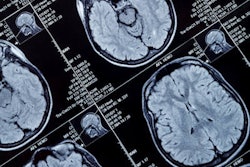

MRI with a diffusion-tensor imaging (DTI) protocol could help clinicians predict when patients who have a genetic mutation that puts them at risk of Alzheimer's disease may develop the condition, according to a study published October 12 in Radiology.

Prescott and colleagues conducted a study that explored whether brain network differences in cognitively normal individuals with ADAD mutations compared to those without them could shed light on Alzheimer's disease progression. The research used data from the Dominantly Inherited Alzheimer Network (DIAN) for 30 mutation carriers and 38 noncarriers; all had healthy cognition when they underwent structural brain MRI and DTI exams.

The investigators found that those study participants with the mutation had less structural connectivity on DTI-MRI scans in the frontoparietal control network part of the brain, which connects two regions understood to be involved with Alzheimer's disease. They also discovered a connection between expected years until onset of symptoms and white matter structural connectivity in this network, even when they controlled for amyloid plaque burden.